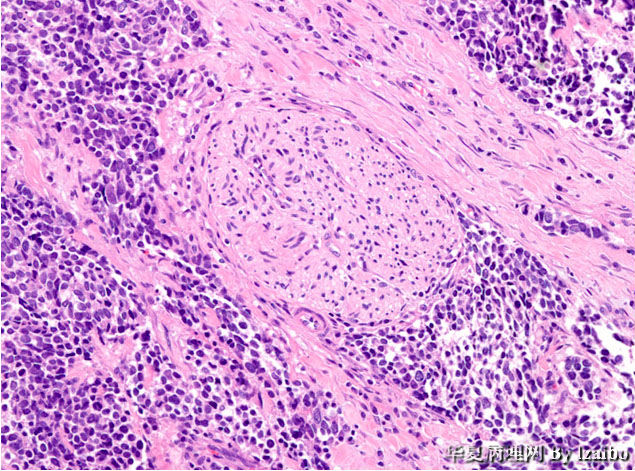

51岁女性表现为慢性疲劳和虚弱持续约6个月。 CT扫描显示左肾脏巨大肿块。病人接受根治性肾切除术。

大体标本描述:肿块位于左肾上极,大小为15×9×8.5厘米。切面上,肿瘤为黄色,并具有散落的白色区域和偶尔出血区,没有明显坏死区。肿瘤非常接近血管,但大体上没有侵入到血管壁。大体上可见肿瘤侵犯输尿管和骨盆(图1和图2)。显微图片(图3-7)。

• 病例1-摘自UPMC Web Cases图7

图7

血管内癌栓,神经累犯,染色质细腻。

首先考虑:1.低分化神经内分泌癌(小细胞癌),原发?or转移?

镜下 肿瘤细胞成巢片状分布,成浸润性生长,侵及神经组织,瘤细胞体积较小,细胞形态呈圆形,椭圆形,短梭形 ,多 角形,核染色质较细腻,核仁不明显,有的隐约可见,胞浆极少。偶就少量的红色胞浆5图,分裂像可见。

诊断 :(左肾上极) PNET.

细胞异型,核沟,坏死,分裂像,血管内瘤栓,神经纤维+-。恶性。

先考虑两个:神经内分泌癌。

诊断:肾神经内分泌癌。

跟在其他解剖部位的神经内分泌肿瘤一样,肾神经内分泌肿瘤可以有不同程度的神经内分泌分化[类癌,非典型类癌,小细胞癌(SCC),大细胞神经内分泌癌(LCNEC)]。肾类癌最常见,为低级别神经内分泌肿瘤,但临床可呈现进展性过程。跟其他解剖部位相似,肾脏小细胞癌和大细胞神经内分泌癌为高度侵略性,远处转移常见,预后极差。

肾类癌和小细胞癌各有自己的组织学特征,病例医生可基于形态学作出准确诊断。神经内分泌分化标记物的免疫染色可用来确认诊断。Synaptophysin是最敏感的神经内分泌分化标记物。也可用其他神经内分泌分化标记物如chromogranin和CD56,但较不敏感。 跟其他神经内分泌肿瘤相比, 大细胞神经内分泌癌较难以诊断,易与高级别肾细胞癌或尿道上皮癌混淆。意识到大细胞神经内分泌癌可发生于肾脏和认真取材可避免误诊。神经内分泌分化标记物的阳性免疫染色和CD10的阴性免疫染色倾向大细胞神经内分泌癌的诊断。